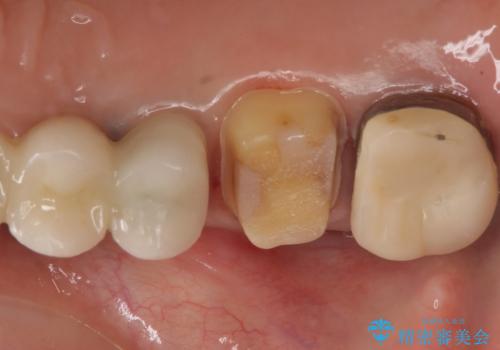

- 左上の奥歯がたまにしみるとのことで来院。視診・レントゲン画像より明らかに劣化した不適な修復物を確認しました。

同じ材料で同じように修復し直してもまた同じような予後になることが予想されるため、適合の良いセラミックインレーでの治療を提案させていただきました。

しかし向かい合わせになる歯の咬みこみが強く、インレーでは破折してしまうリスクが高いと予想し、より強固なクラウンで修復することになりました。